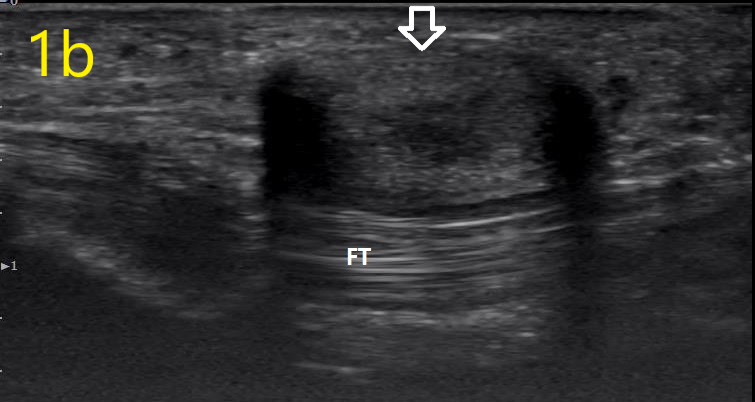

Image 1b

Ultrasound in Orthopedic Practice